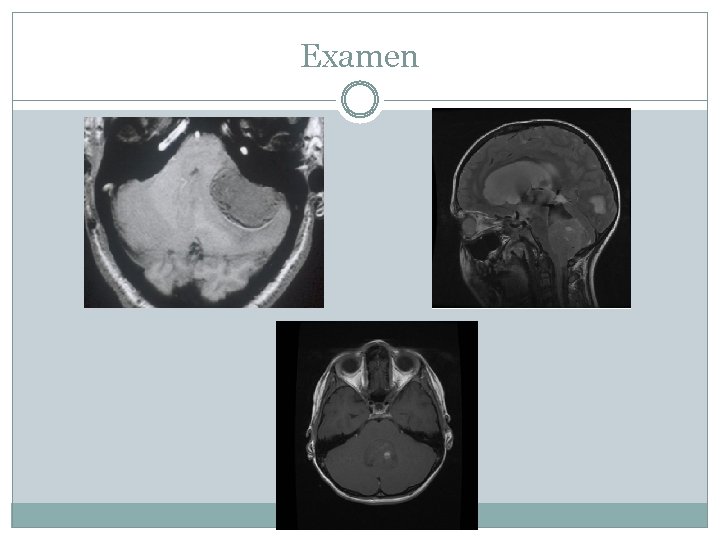

Examen Faire IRM cérébrale et spinale+ cytologie du LCR Biopsie mais préférer la Chirurgie d’exèrese En post chirurgie: -IRM post opératoire à 72 h -IRM spinale et cytologie LCR à 14 jours (Chang 1989)

Examen